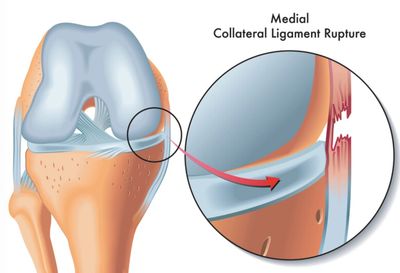

A medial collateral ligament tear, or more commonly known as an MCL tear, occurs when there is damage to the medial collateral ligament, located on the inner part of the knee. This ligament is about 8-10 cm in length and connects the femur to the tibia, in addition to providing strength and stability to the knee join. A sudden and forceful twist and turn in the knee or direct hit to the outer part of the knee can cause a partial or complete tear in the ligament. MCL tears can be categorized into 3 grades: